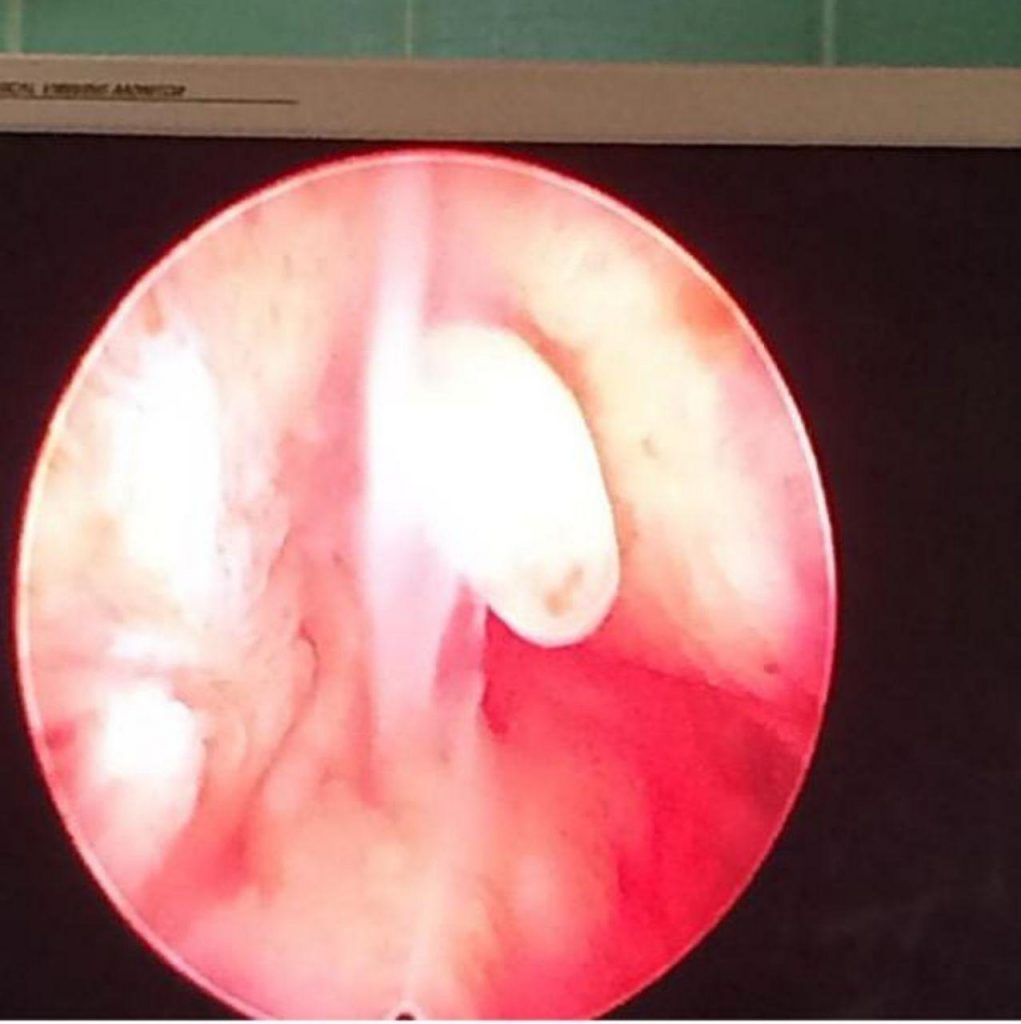

انجام لاپاروسکوپی های تشخیصی و درمانی

کیست تخمدان و هیسترکتومی یا خارج سازی رحم

به روش لاپاروسکوپی با حداقل درد و بخیه